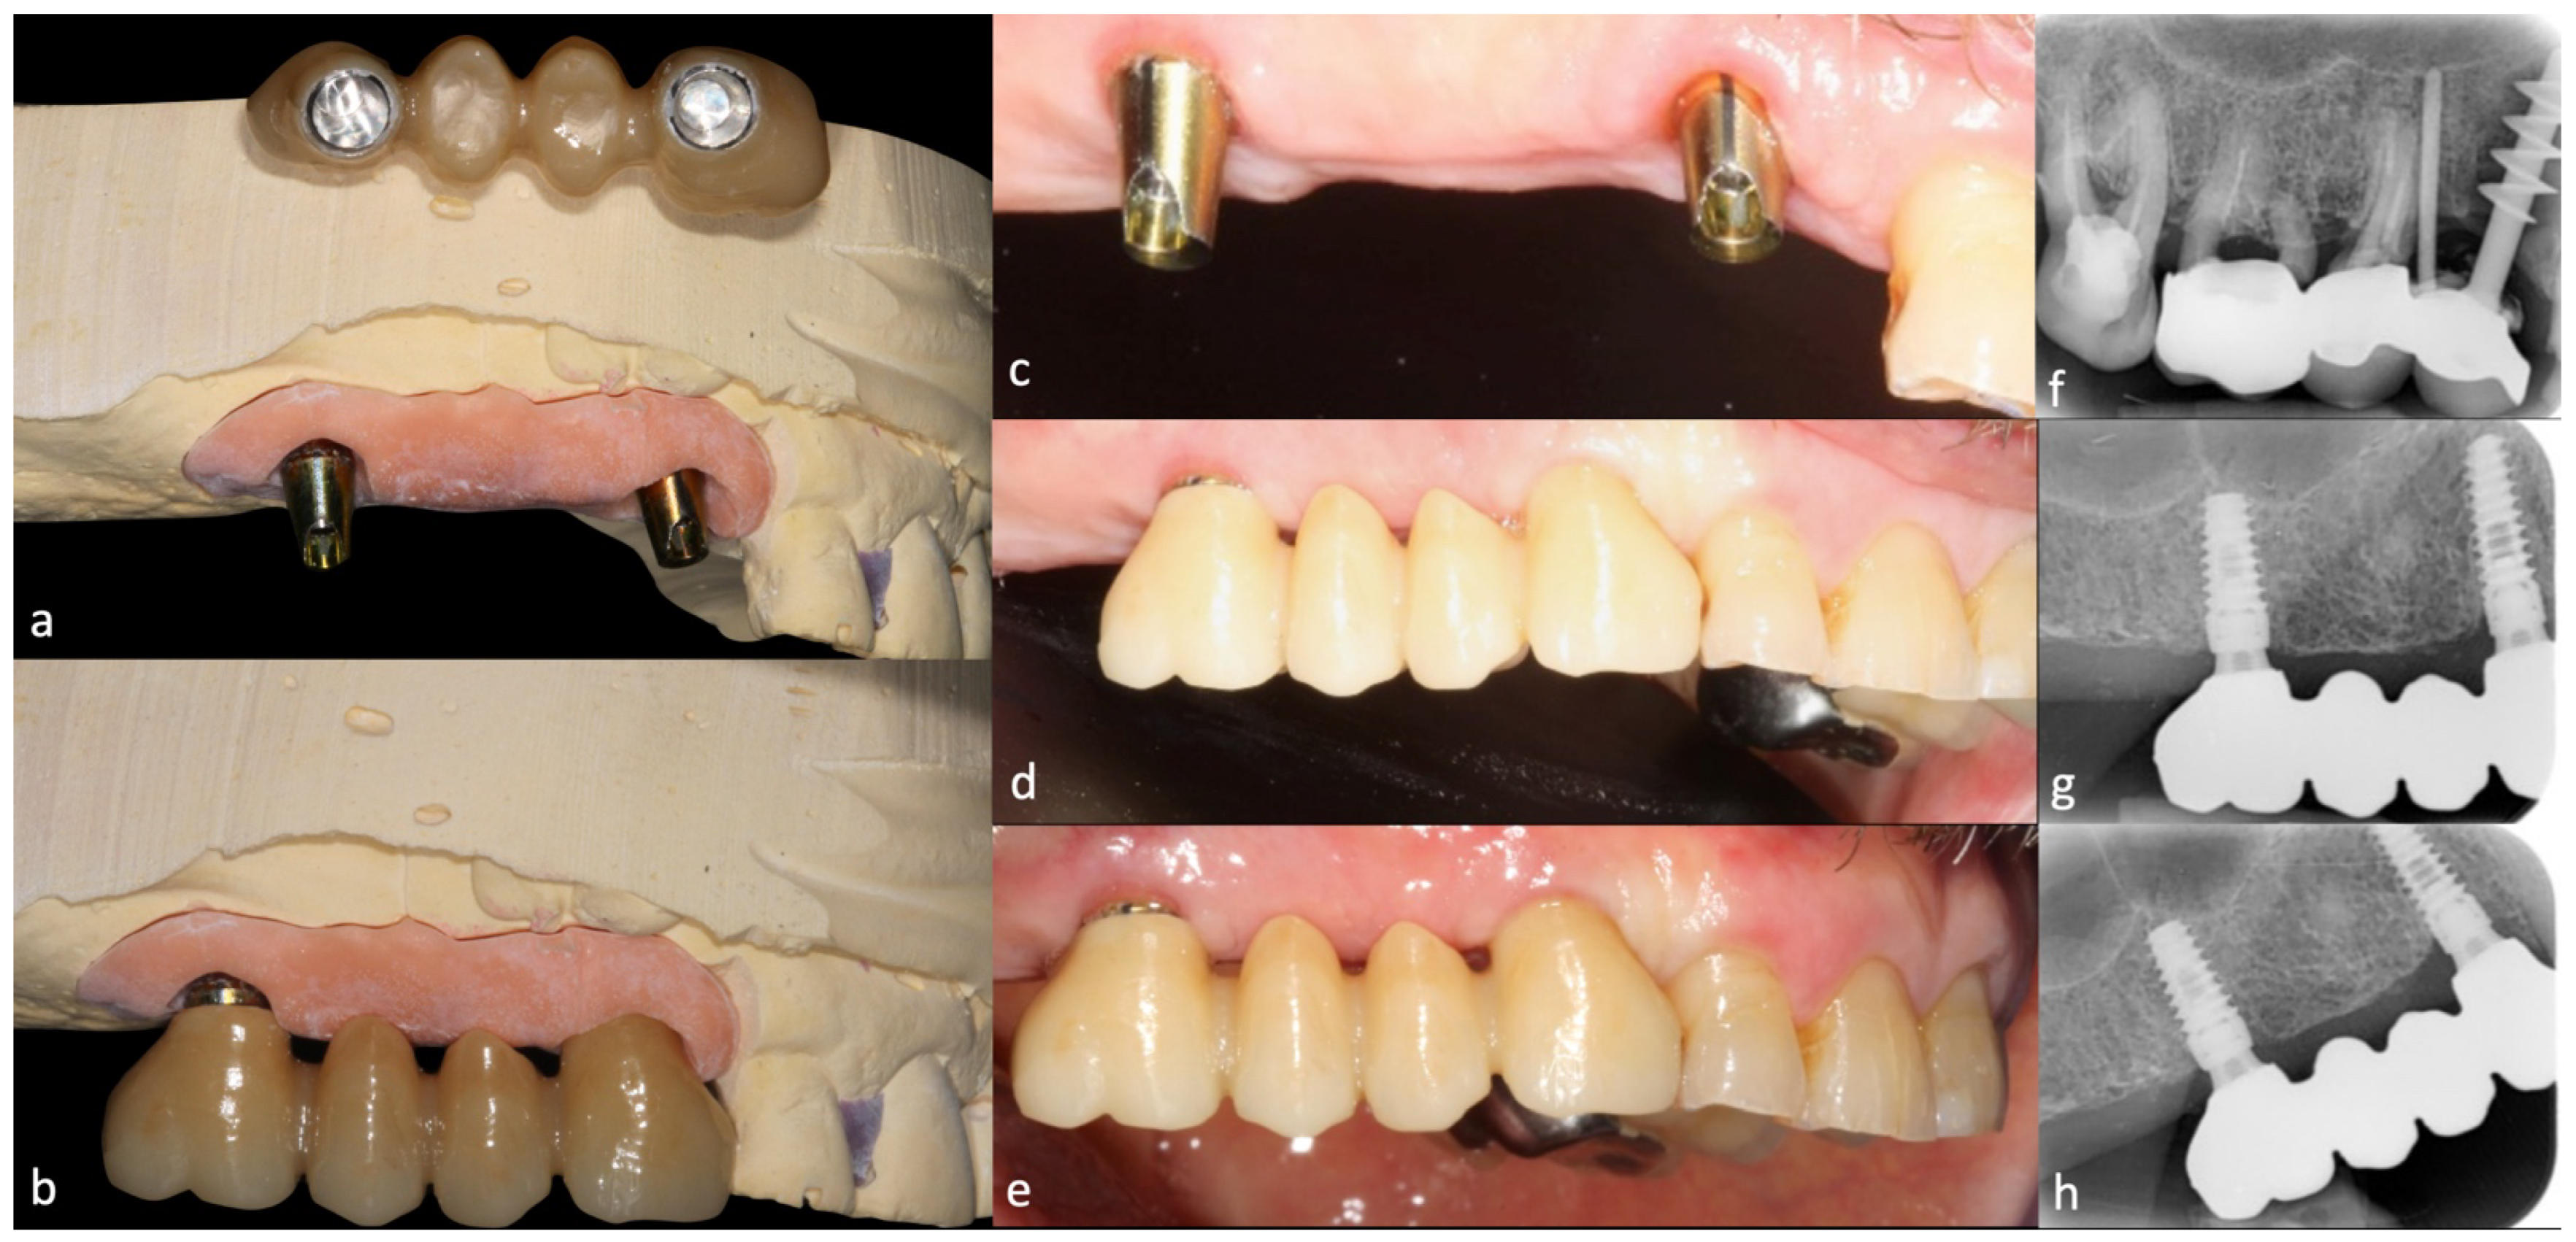

1. Introduction

2. Materials and Methods

2.3. Prosthetic Protocol

2.4. Follow-Up

3. Results